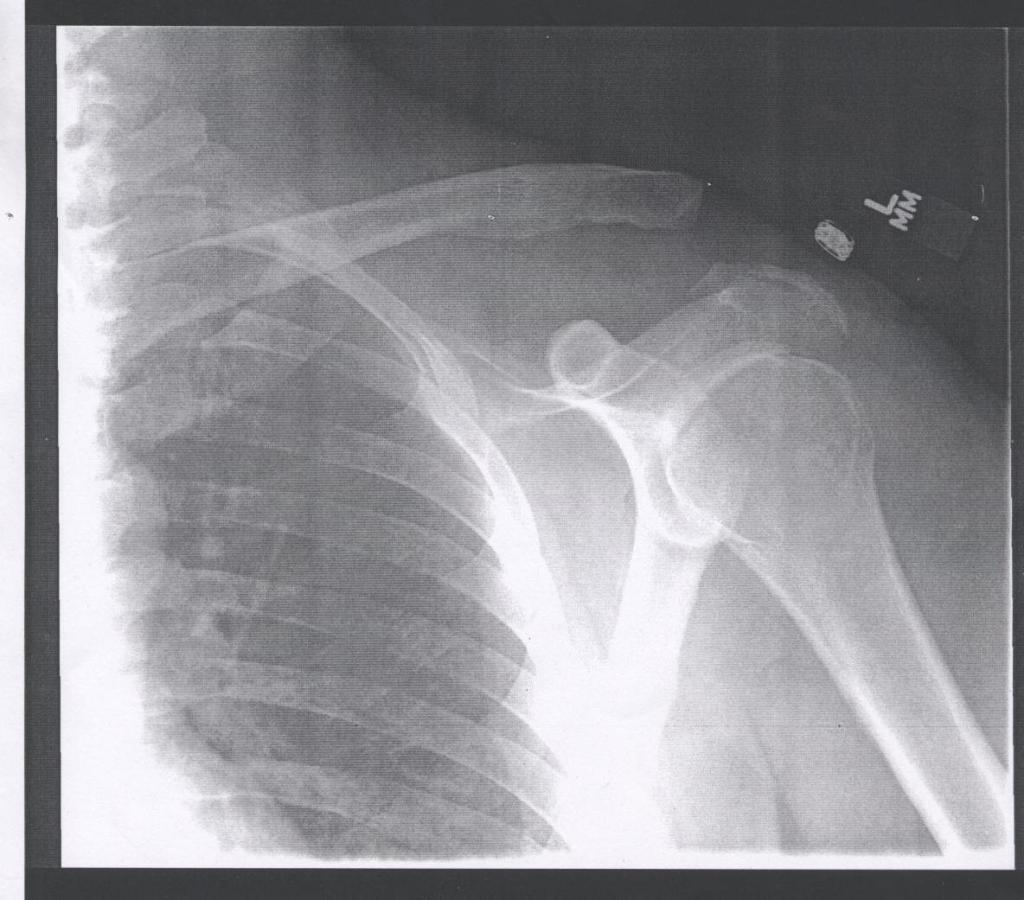

Screw is out. Fuzzy head is clearing. Ah, to have range of motion again, what a treat. Doc says, “Take it easy for the first few days, and no contact sports for 3 months’. Like I haven’t been taking it easy for years and the last ‘contact’ sport I played was air hockey at that bar in Mt. View (still table Champion!). Unless you count getting hit by your own golf ball off a tree ricochet a contact sport? Whatever.

Here’s the $385 dollar screw in question –

Yes, it’s a Phillips head. No, he didn’t use an electric screwdriver. Yes, I’m going to make a keyring out of it. And yes, it really cost 385 bucks – Wanna know why your healthcare insurance is so expensive?